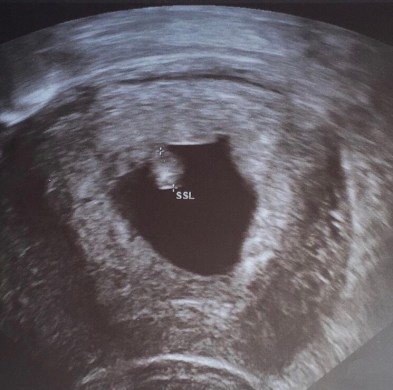

Nach zwei weiteren Schwangerschaftstests, die ich dann zwei und vier Tage später noch durchgeführt habe (ich hatte noch Vorrat, irgendwas muss man ja damit anstellen – natürlich NUR deshalb und ihr wisst ja, sicher ist sicher ;-)) habe ich ihm dann geglaubt, spätestens dann aber als wir unser erstes Foto beim Frauenarzt bekommen haben. Es war ein pochendes Etwas zu sehen – das pochende kleine Herzchen unseres ersten Babys.